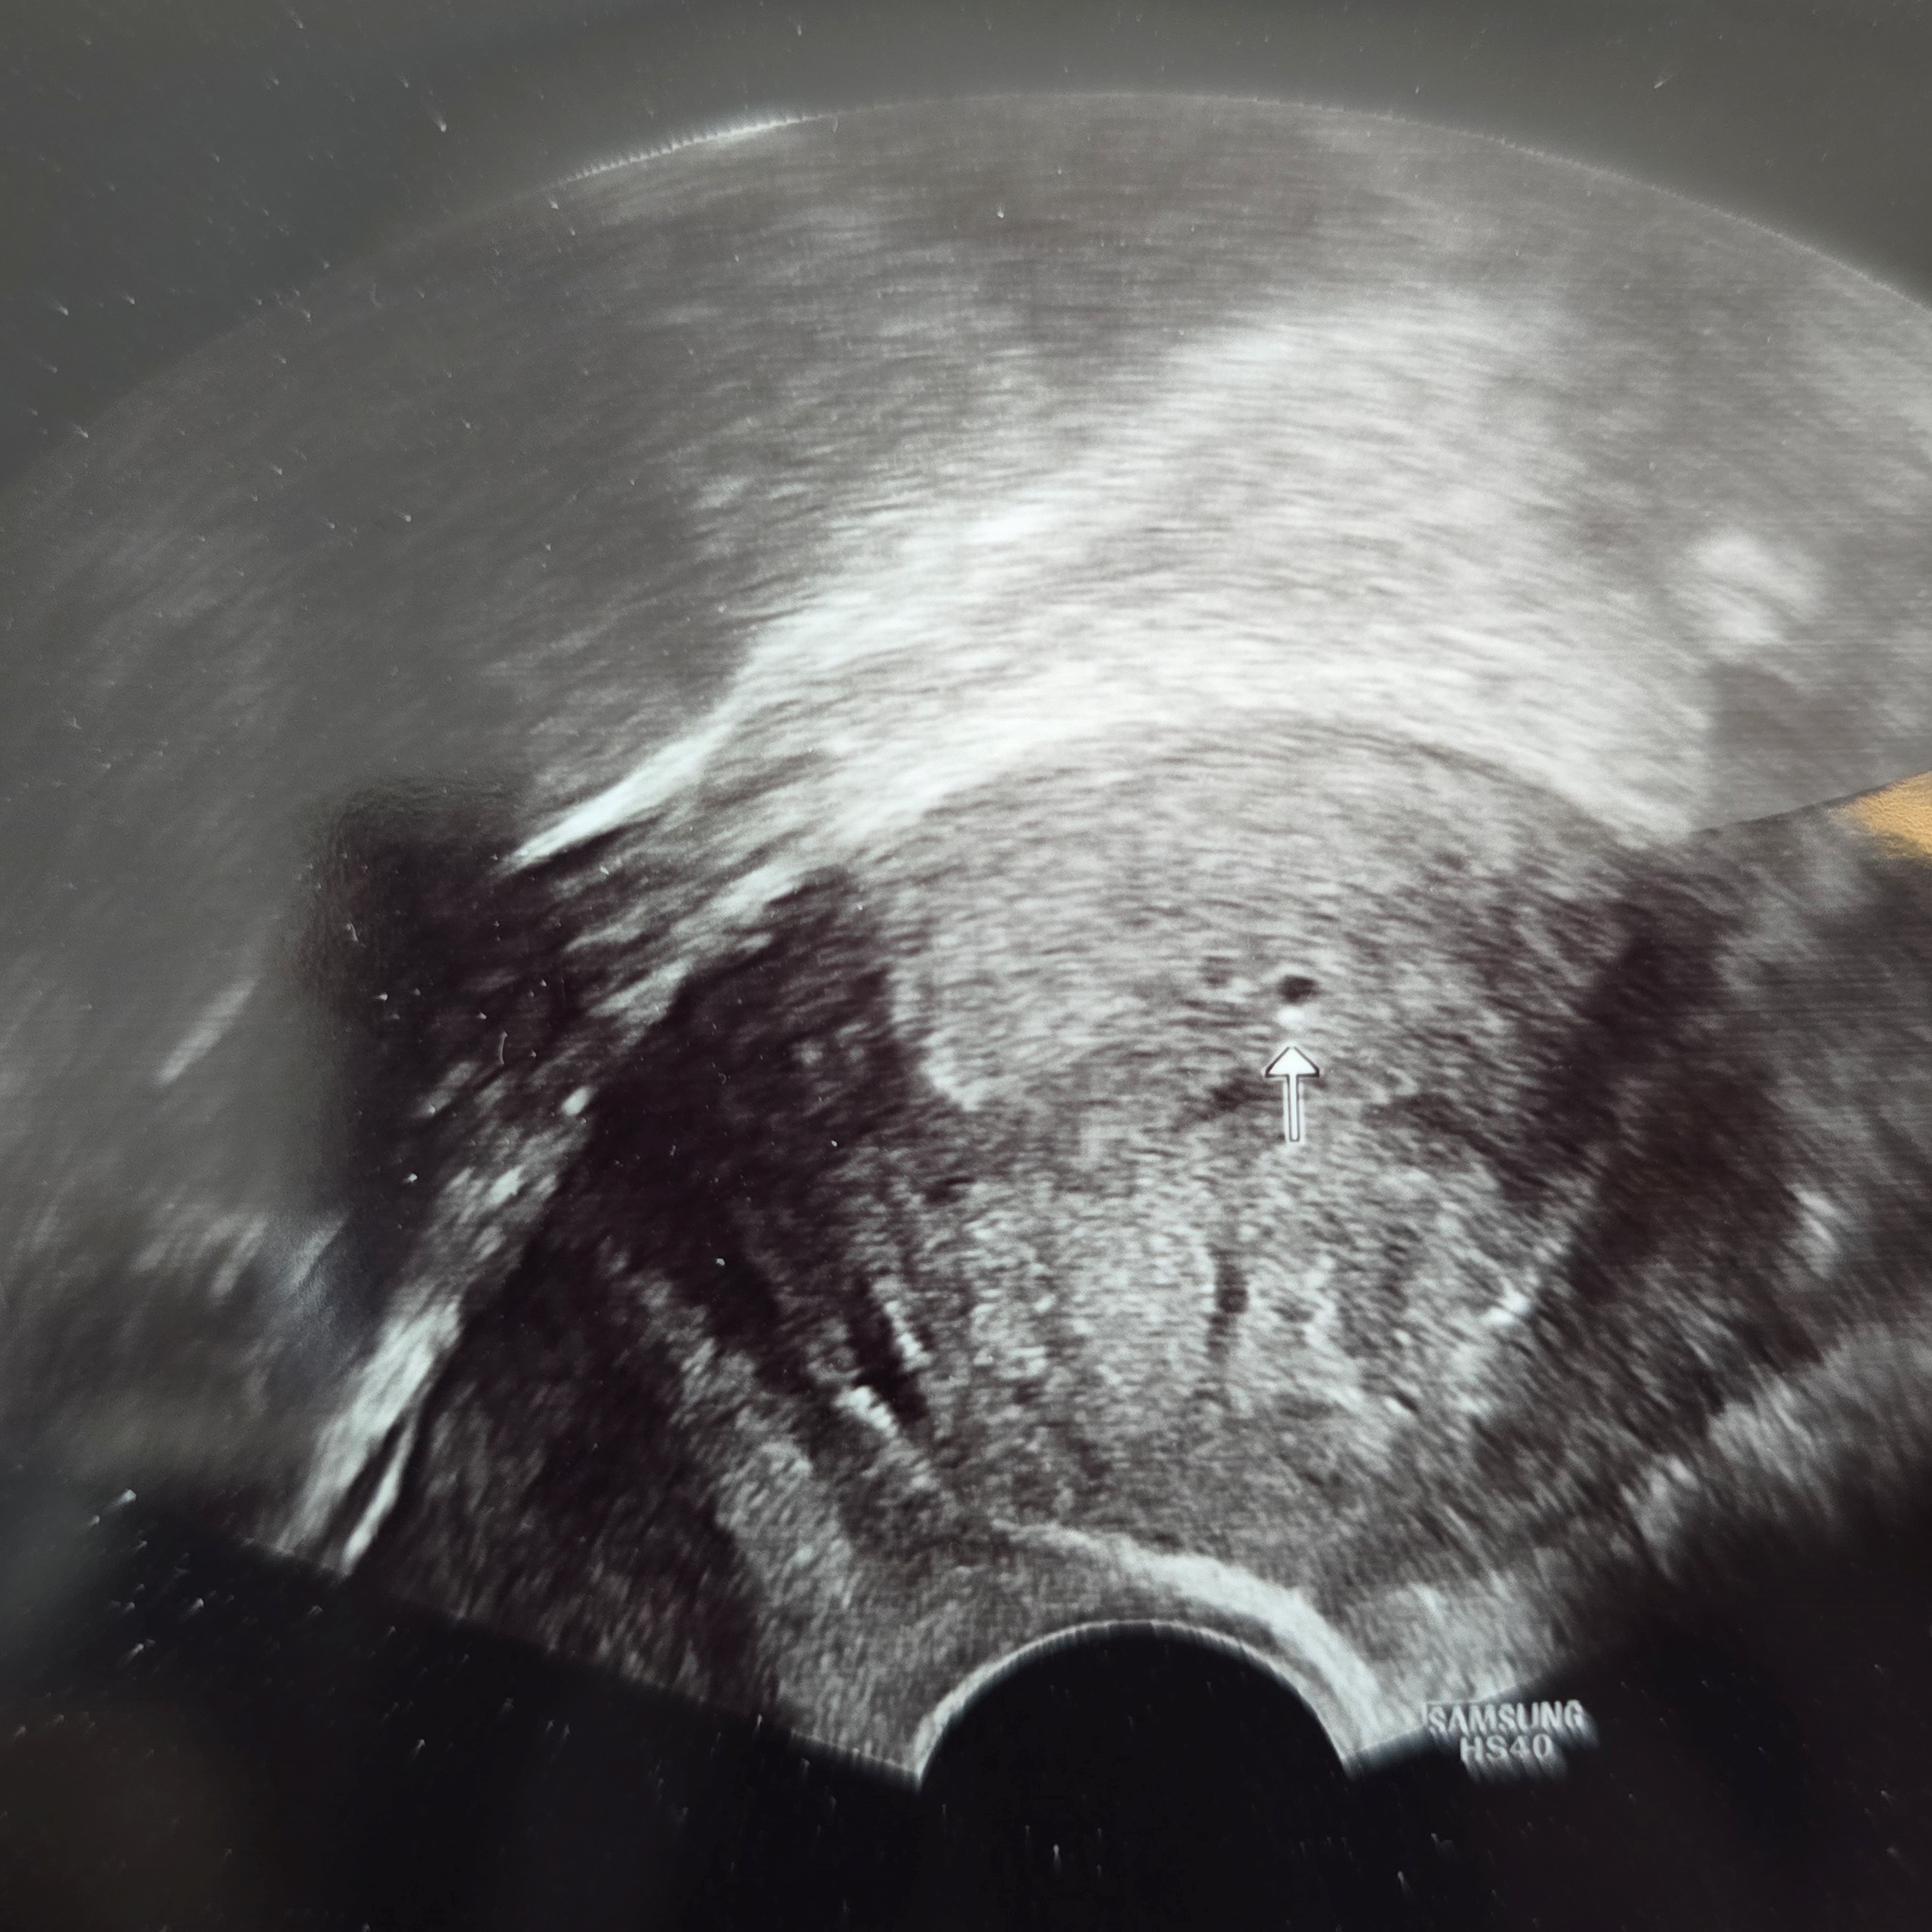

이식 17일 차 5주 차 - 3차 피검사 및 초음파

피검사를 하고 초음파를 보자고 하셨다.

걱정하며 본 초음파엔 아기집이 빼꼼~!!!!!!!

선생님께서 이건 아기집이 확실하다면서 아기집 생겼다고

자궁 외 임신은 아니라고 걱정 말라고 하셨다!!!!!!!

진짜 아기집 보는데 며칠동안 했던 걱정이 싹 내려가면서

눈물이 고였다.ㅠㅠ

5주 차라기엔 아기집이 조금 작지만 따라가는 경우가 있으니

일주일 뒤에 다시 한번 보자고 하셨다.ㅎㅎ

착상이 조금 늦은 아가니까 다음 주에도 잘 커있을 거라고 믿고 설레는 마음으로 기다리려 한다.ㅎㅎ

피검은 587.3!!!

1차 피검사 61.73에서 2차 피검사 99.14는 더블링 실패지만

2차 피검사 99.14에서 3차 피검사 587.3 까지는 2배로 잘 더블링이 된걸 보니 이렇게 기쁠 수가 없다.ㅎㅎ